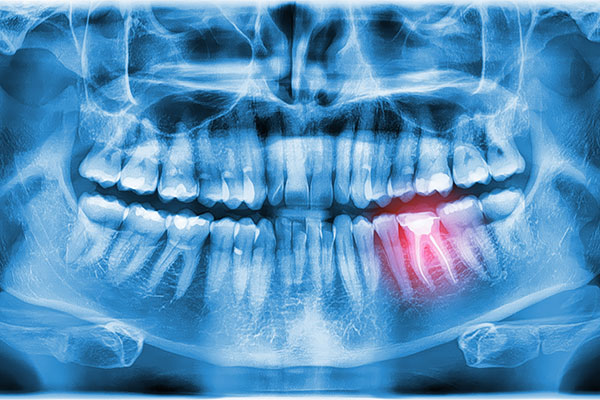

Dentures are custom-made artificial teeth and gums that form to your mouth to replace lost or removed teeth. In most cases, dentures are removable. They are generally made of porcelain or hard resin and can be either complete dentures or partial dentures.